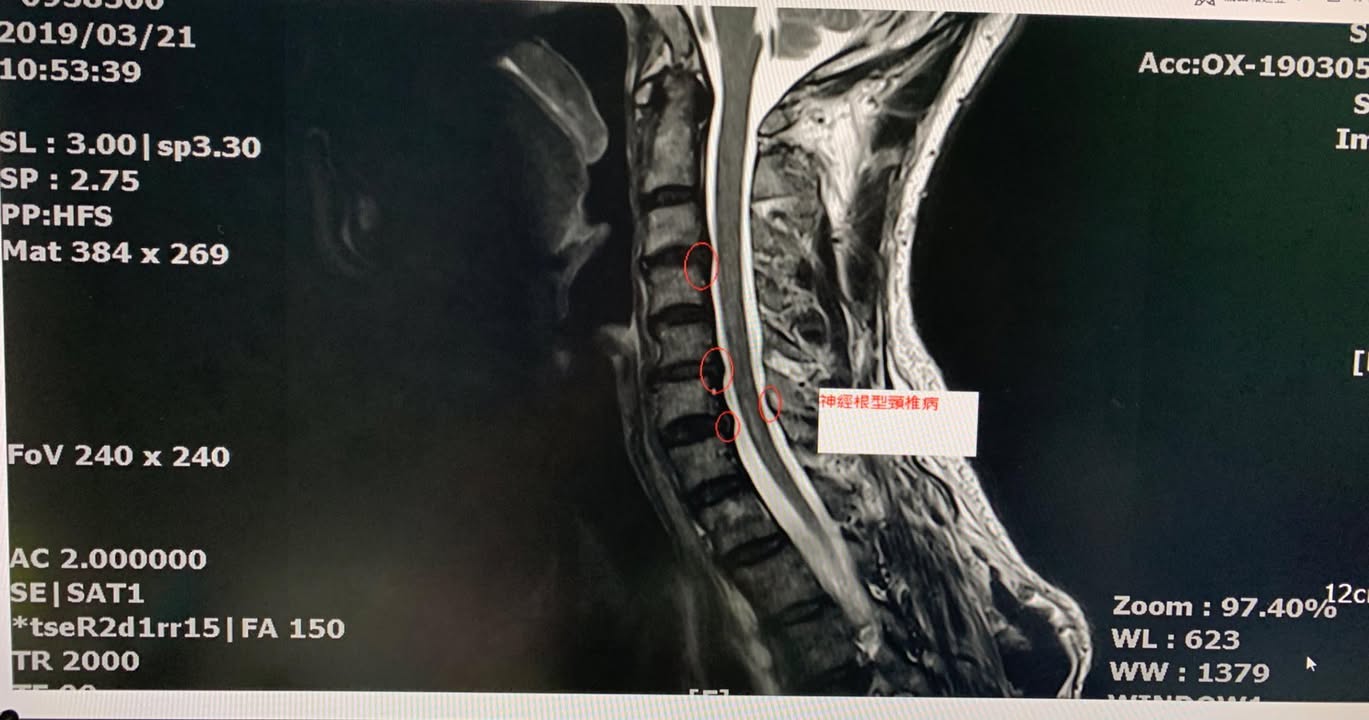

宜蘭的于大哥抱怨左邊頸痛連肩膀,大約半年,頭往後抬最明顯,會有明顯上臂麻痛感,之前長期是衝浪愛好者,需要密集使用頸部肌肉群,一開始只是肩膀痠痛,後來發現衝浪抬頭整條手臂就開始麻痛才覺得不對勁,之前嘗試貼過草藥有一點效果,但是一直沒有重大改善,去當地的醫學中心接受頸椎mri核磁共振照影顯示頸椎間盤輕微突出導致神經根卡壓(如圖),經過衝浪客介紹特地北上接受頸椎整合中醫微創療法,非常幸運四次效果就很明顯,這中間去衝浪發現手的麻痛感大幅度降低,非常開心,這次治療好徐醫師提醒頸部跟肩膀肌肉要適時放鬆跟強化頸部深層肌肉的力量才不會再度復發